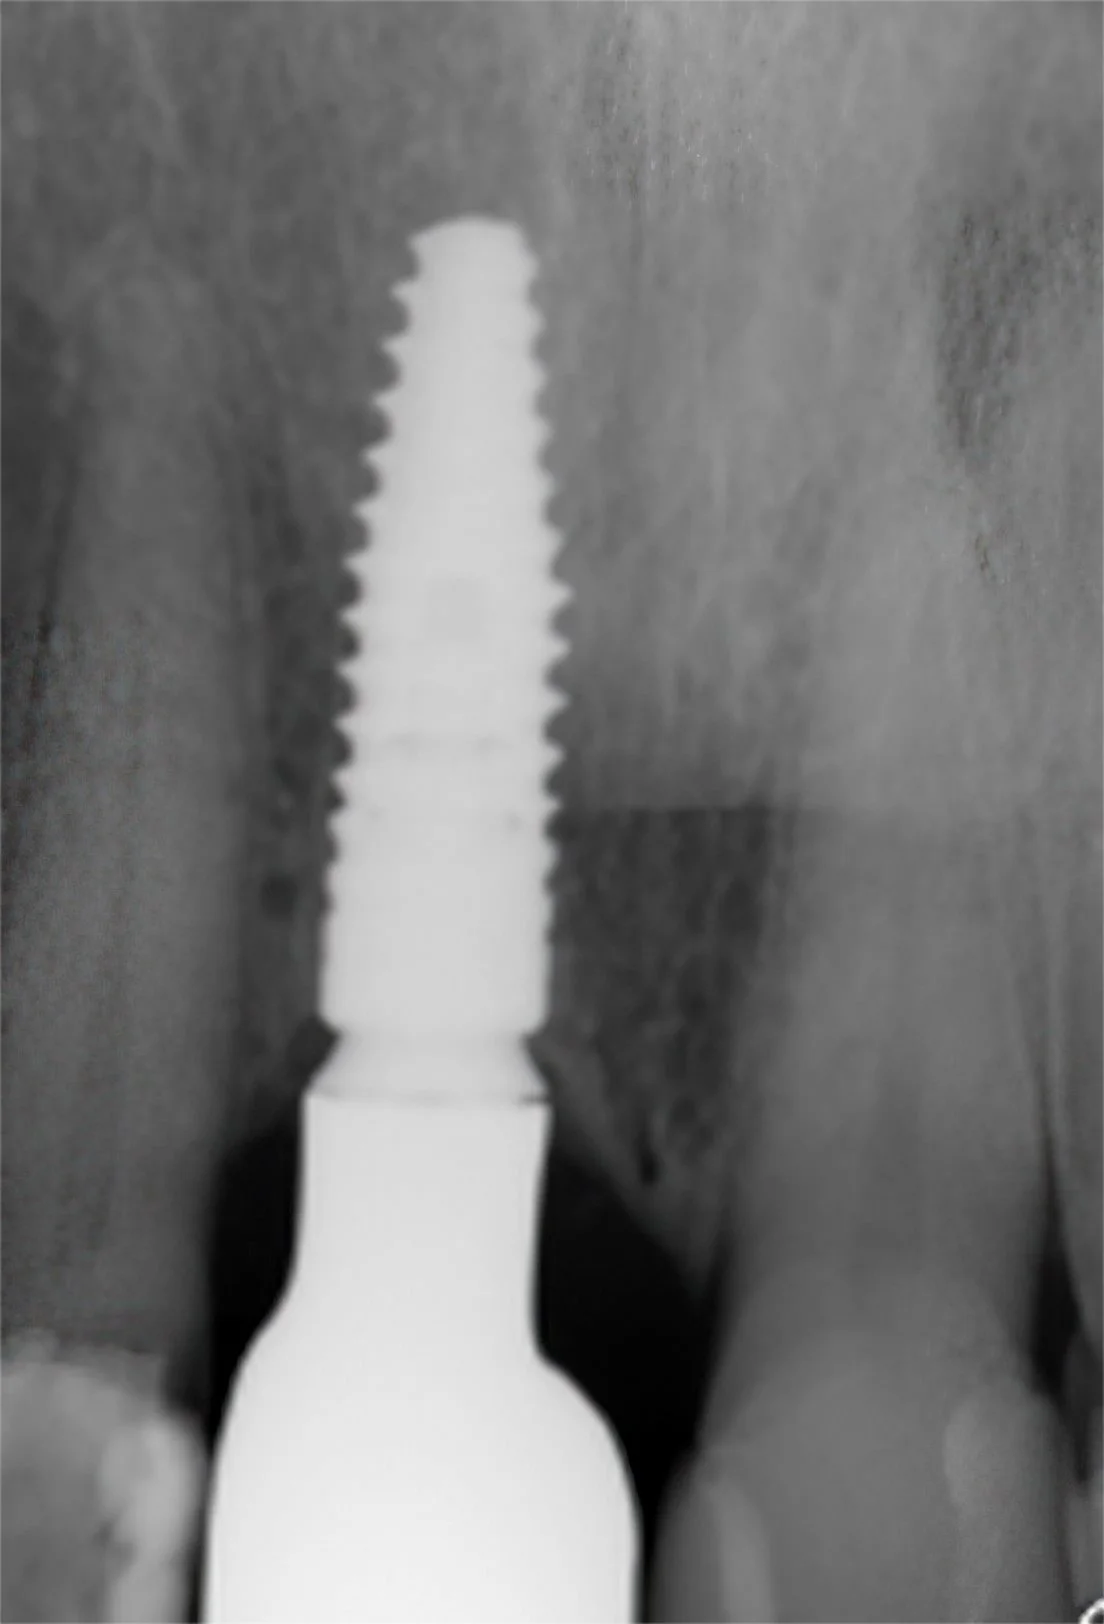

This 70 year old patient was referred to me at Lismore in 2024 by a Ballina dentist to complete an implant crown

-

after an Oral Surgeon placed a Straumann implant fixture and healing abutment/cap

The implant crown was secured into place and torqued

The final photograph on the day of fitting the implant crown in 2025 and colour matched with the adjacent filled left front tooth